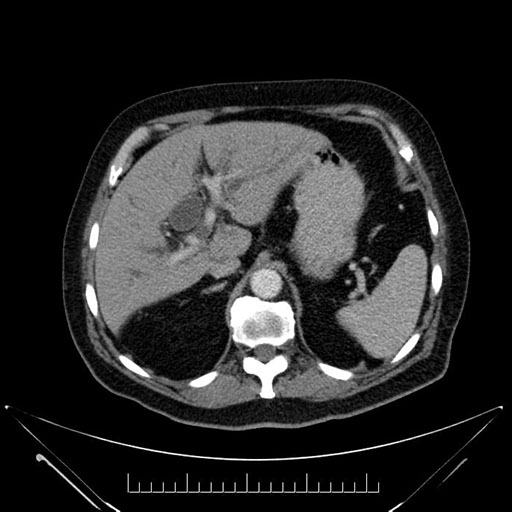

Whipple (pancreaticoduodenectomy) [case 7]

Imaging Analysis

Look through the patient's CT scan to identify any areas of concern for the necessary procedure.

Based on your CT findings, which issue(s) would give reason for "planned slowing down moment(s)" in this case?

Considering a standard Whipple procedure, what step(s) of the operation would you do differently in this case?